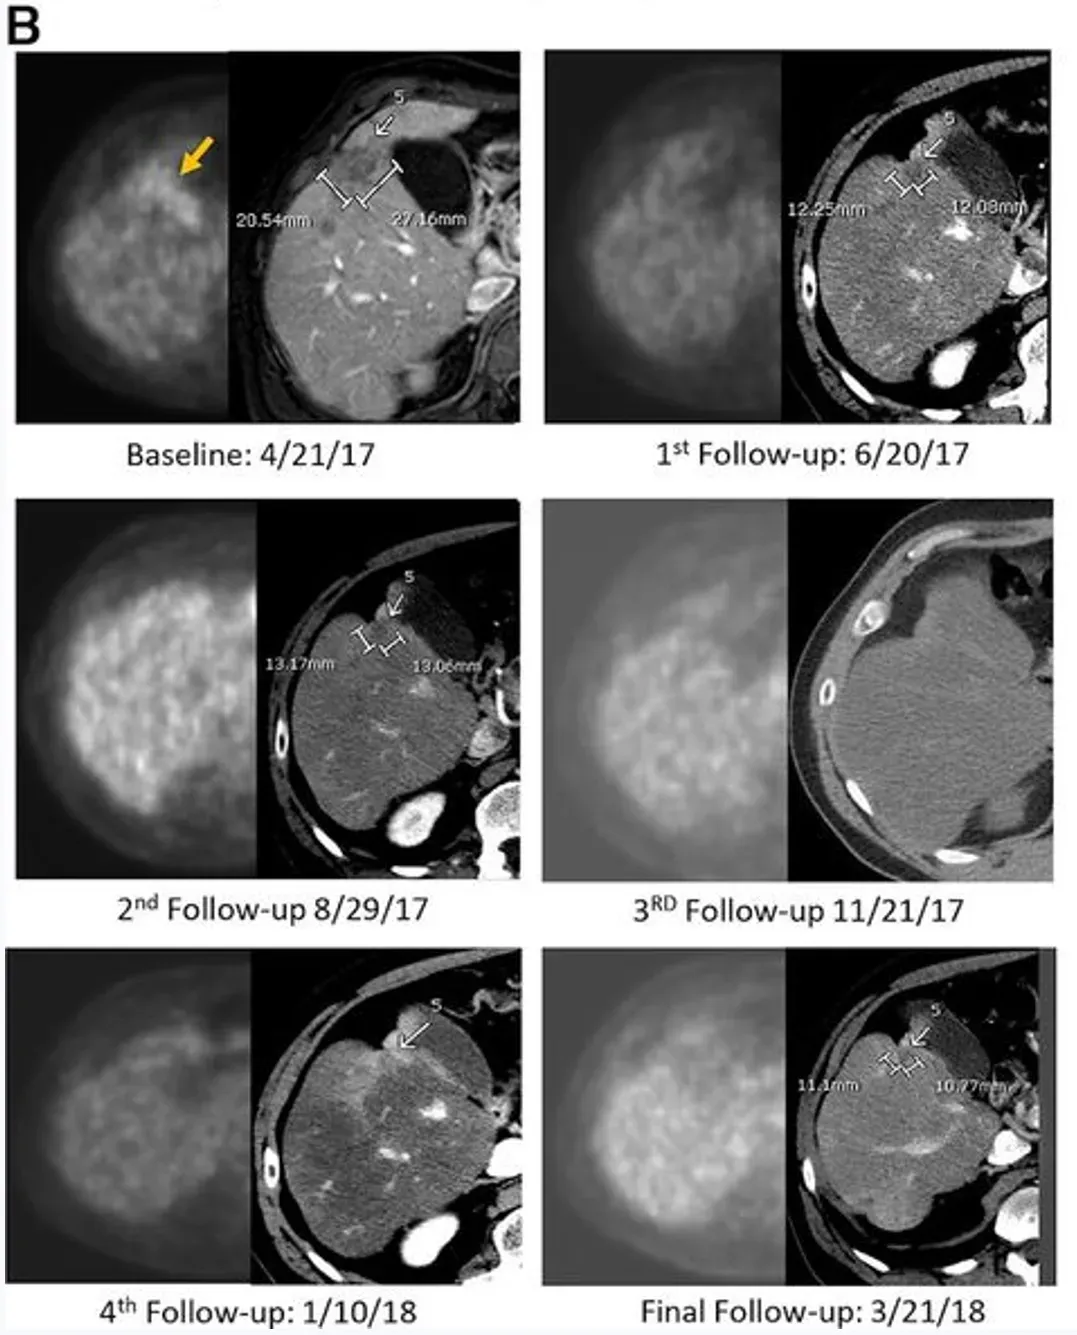

下图展示了一例59岁男性Kras突变型直肠癌患者的影像对比图:该患者既往接受过3线治疗,在接受IM96 CAR-T治疗后,其肺部、肝部的转移病灶均显著缩小。

近期,《癌症免疫治疗杂志》报道了一则振奋人心的案例(NCT02850536):一名50多岁男性患者,确诊为持续性低分化胰腺腺癌伴肝转移,美国东部肿瘤协作组(ECOG)体能状态评分为0分,此前接受过一线标准全身化疗(5-氟尿嘧啶、亚叶酸钙、伊立替康、奥沙利铂联合的FOLFIRINOX方案),因治疗耐药入组,接受了第二代抗CEA CAR-T疗法联合低剂量白细胞介素-2(IL-2)治疗。

治疗结果显著:CAR-T输注6周后,正电子发射断层扫描(PET-CT)显示肝脏内原氟脱氧葡萄糖(FDG)阳性病灶完全无代谢活性,该完全代谢反应持续13个月;静脉增强CT提示目标病灶稳定或略缩小,无新增转移灶。治疗3.7个月时,PET扫描显示肝脏仍维持无代谢活性,但胰头原发灶代谢活性升高,患者随即接受以5-氟尿嘧啶为放射增敏剂的胰腺肿块放疗,后续扫描显示原发肿瘤灶亦达到完全代谢缓解。

从生存期来看,该患者总生存期(OS)长达23.2个月——而多数IV期胰腺腺癌患者中位生存期仅5个月,意味着CEA CAR-T疗法让这位化疗耐药患者的生存期延长了近5倍(4.64倍)。

肿瘤标志物层面,以治疗中最低点计算,患者CEA下降81%、糖类抗原19-9(CA19-9)下降68%,且两类标志物均在治疗后2-3个月内恢复正常。病理分析进一步显示,肝肿瘤活检标本出现大面积透明纤维化,无正常肝组织损伤迹象,且标本中检测到大量CAR+细胞。

这一案例证实,区域输注CAR-T疗法对当前免疫治疗成功率低的胰腺腺癌肝转移等适应症,兼具生物活性与安全性,为这类患者带来了新的治疗曙光与选择。